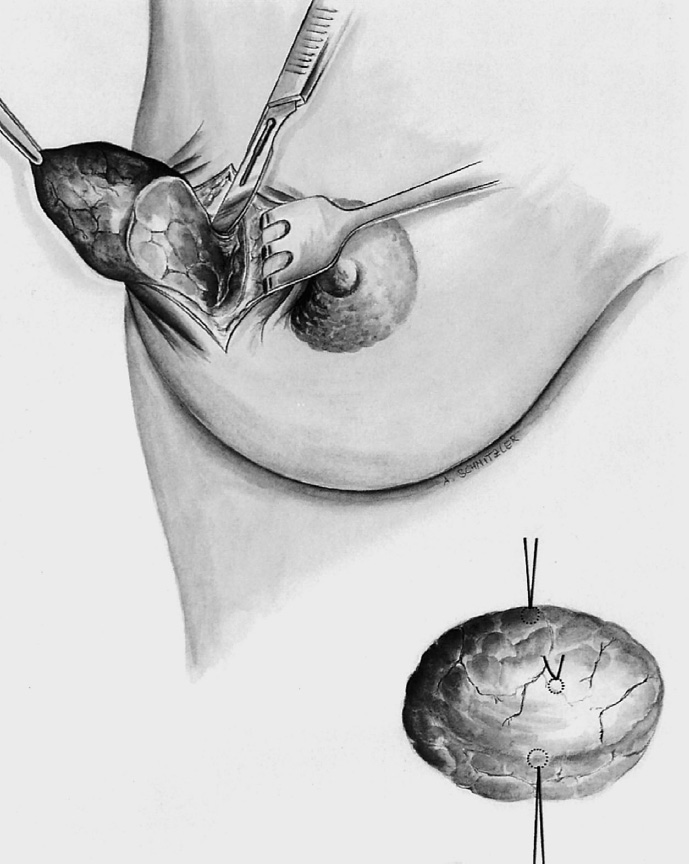

After complete resection of the segment containing the tumor, the specimen is marked with three sutures to provide precise three-dimensional spatial orientation for the pathologist, stating the exact location of the tumor in the breast (e.g., left breast at the 2-o’clock position, 5 cm from the nipple)—a specimen sonogram or mammogram is performed.

The tumor bed is marked with clips for accurate radiotherapy planning.

The former tumor region is marked with titanium clips (usually three clips for spatial orientation).

The former tumor region is marked with clips.

The former tumor bed is marked with clips for optimized postoperative radiotherapy.

The breast containing the tumor is resected in classic segmental fashion along the tumor axis. In purely cosmetic reduction, tissue is removed mainly in the upper outer part and somewhat less in the superior and medial part. It is important to leave sufficient breast tissue behind the areola and in the cranial part as otherwise the projection of the areolar region will be poor after it is sutured. Additional tissue can be resected lateral to the inferior pedicle on right and left.

The skin is approximated subdermally in the region of the vertical limb in preparation for reconstruction of the reduced breast with chest wall fixation and repositioning of the nipple.

The breast is fixed to the pectoralis muscle to avoid postoperative lateral deviation of the “new” breast. The de-epithelialized dermis covering the inferior central pedicle is sutured to muscle in a superolateral and superomedial direction using absorbable sutures (Vicryl 0, 2–0). It is useful to draw down the new skin envelope over the “new” breast to determine its optimal position on the chest wall.

After establishing the final position of the nipple–areola complex, the marked area of skin is excised precisely over the nipple. To facilitate positioning, a retaining suture can be placed in the nipple at the 12-o’clock position; this allows assessment of any tension on the nipple (e.g., due to the internal fixation). Following skin excision, the nipple can be readily guided to its new position using the retaining suture.